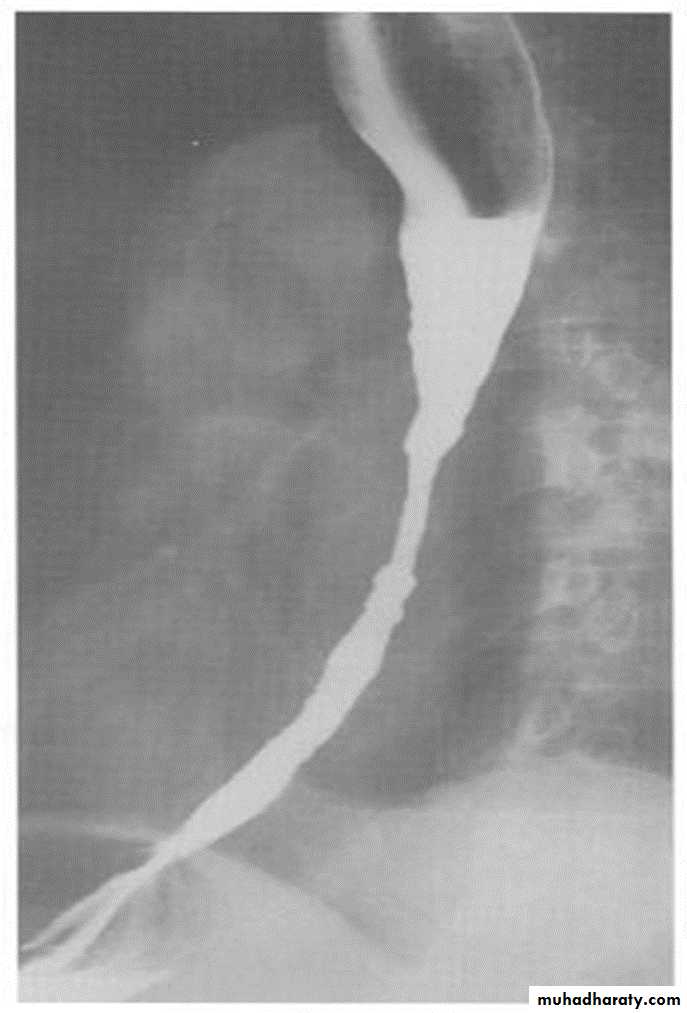

Annular Carcinoma

Narrowing :

1-Constant.

2-Irrigular .

3-Variable length.

4- Shouldering sign.

5-Fistula (double tract).

6-Soft tissue shadow of the mass